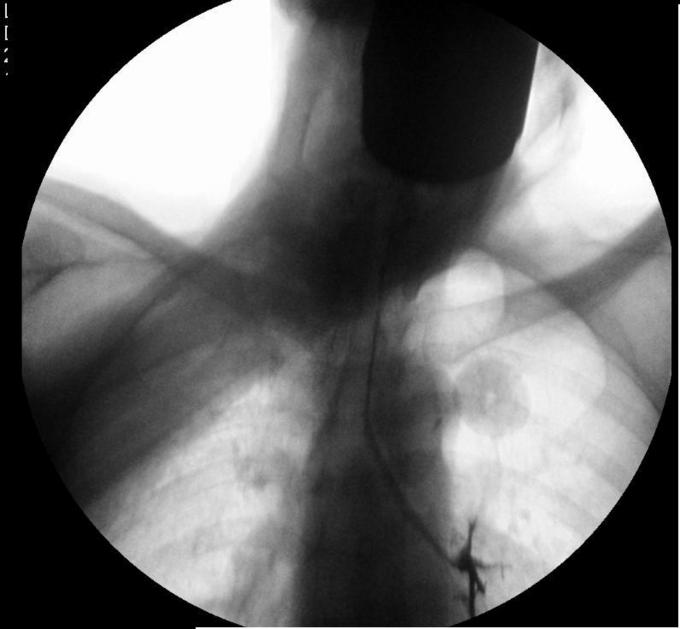

钡餐误吸

吞咽困难查因 安排吞钡试验

患者白日行钡餐检查,夜间出现呼吸困难,血氧饱和度下降,考虑存在1型呼吸衰竭 讨论: 1.目前针对钡餐误吸性肺炎的治疗措施哪些有意? 2.如何预防本次事件?